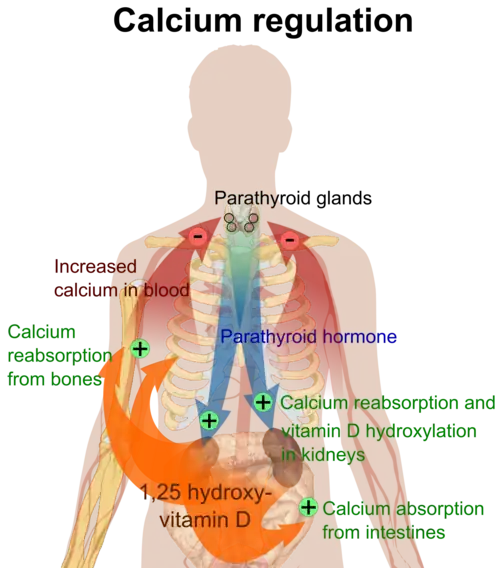

Activation of VDR in the intestine, bone, kidney, and parathyroid gland cells plays a crucial role in maintaining calcium and phosphorus levels in the blood, a process that is assisted by parathyroid hormone and calcitonin, thereby supporting bone health.[1][16][4] VDR also regulates cell proliferation and differentiation. Additionally, vitamin D influences the immune system, with VDRs being expressed in several types of white blood cells, including monocytes and activated T and B cells.[17]

Vitamin D metabolism is regulated not only by the negative feedback mechanism of calcitriol but also by two hormones: parathyroid hormone (PTH) and fibroblast growth factor-23 (FGF-23). These hormones are essential for maintaining the body's calcium and phosphate balance.[206]

Parathyroid hormone (PTH) regulates serum calcium through its effects on bone, kidneys, and the small intestine.Bone remodeling, a constant process throughout life, involves bone mineral content being released by osteoclasts (bone resorption) and deposited by Added internal link to Osteoblast. PTH enhances the release of calcium from the large reservoir contained in the bones. It accomplishes this by binding to osteoblasts, in this way inhibiting the cells responsible for adding mineral content to bones, thus favoring the actions of osteoclasts.[219] In the kidneys, around 250 mmol of calcium ions are filtered into the glomerular filtrate per day, with the great majority reabsorbed and the remainder excreted in the urine.[220] PTH inhibits reabsorption of phosphate (HPO42−) by the kidneys, resulting in a decrease in plasma phosphate concentration. Given that phosphate ions form water-insoluble salts with calcium, a decrease in the phosphate concentration in plasma (for a given total calcium concentration) increases the amount of ionized (free) calcium.[219] A third important effect of PTH on the kidneys is stimulation of the conversion of 25-hydroxy vitamin D into 1,25-dihydroxy vitamin D (calcitriol).[219] This form of vitamin D is the active hormone which promotes calcium uptake from the intestine via the action of calbindin.[221] Calcitriol also reduces calcium loss to urine.[218]

Per the diagram, calcitriol suppresses the parathyroid hormone gene, thus creating a negative feedback loop that combines to tightly maintain plasma calcium in a normal range of 2.1-2.6 mmol/L for total calcium and 1.1-1.3 mmol/L for ionized calcium.[212] However, there are also vitamin D receptors in bone cells, so that with serum vitamin D in great excess, osteoclastic bone resorption is promoted regardless of PTH, resulting in hypercalcemia and its symptomology.[222]